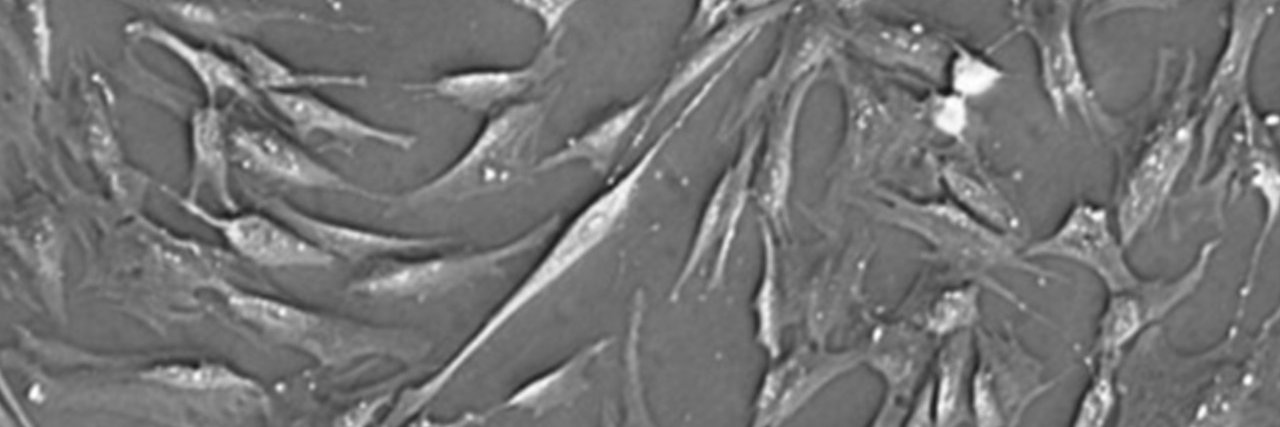

REVERSE AGING. ELIMINATE CANCER. REJUVENATE ORGANS.

Immorta Bio Doubles Mouse Lifespan Using Combination Senolytic and Regenerative Therapy in Validated Aging Models @ImmortaBio prnewswire.com/news-releases/…